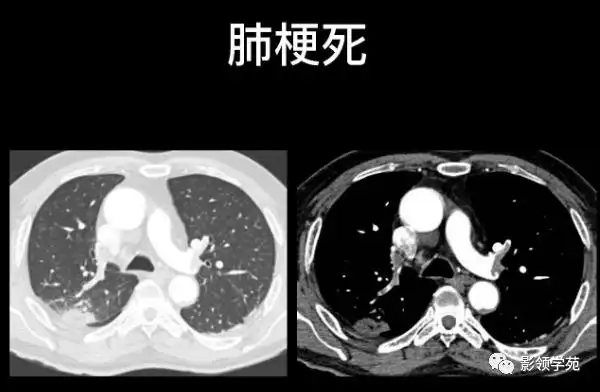

肺栓塞的影像诊断与鉴别诊断

图片示:左下肺动脉栓塞